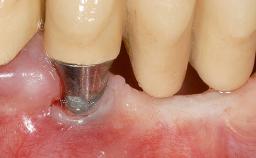

Soft-Tissue Volume Augmentation Using a Connective-Tissue Graft Harvested from the Maxillary Tuberosity

Soft Tissue Grafting Simultaneous